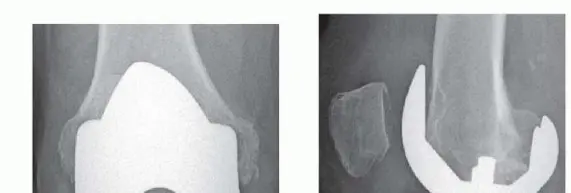

أ. جراحة مراجعة استبدال مفصل الركبة الكلي (Revision Total Knee Arthroplasty - rTKA)

هذه هي الجراحة الأساسية لمعالجة فشل استبدال الركبة الأولي وفقدان العظم. تتضمن إزالة المكونات الاصطناعية القديمة التالفة، وتنظيف المنطقة من أي أنسجة ملتهبة أو مصابة، ثم إعادة بناء العظم وزرع مكونات مفصل ركبة صناعي جديد.

ب. تقنيات معالجة عيوب العظم (Bone Defect Management)

تعتبر معالجة عيوب العظم هي جوهر جراحة المراجعة، وهي تتطلب خبرة ودقة عالية. يستخدم الأستاذ الدكتور محمد هطيف أحدث التقنيات لضمان أفضل النتائج:

-

1. ملء الأسمنت العظمي (Cement Filling):

- متى يستخدم؟ في حالات فقدان العظم الصغيرة والمحدودة (عيوب من الدرجة الأولى أو الثانية حسب تصنيف Anderson Orthopaedic Research Institute - AORI).

- المبدأ: يتم استخدام الأسمنت العظمي لملء الفراغات الصغيرة أو العيوب السطحية في العظم، مما يوفر سطحًا مستويًا لتثبيت المكونات الاصطناعية الجديدة.

- المزايا: بسيط نسبيًا، يوفر تثبيتًا فوريًا.

- العيوب: لا يعوض العظم المفقود بيولوجيًا، وقد لا يكون كافيًا للعيوب الكبيرة.

2. الدعامات المعدنية (Metal Augments/Wedges/Blocks):

- متى تستخدم؟ في عيوب العظم المتوسطة (عيوب AORI من الدرجة الثانية).

- المبدأ: هي قطع معدنية مصممة خصيصًا يتم تثبيتها بالعظم لتعويض العظم المفقود وتوفير قاعدة صلبة لتثبيت المكونات الاصطناعية. تأتي بأشكال وأحجام مختلفة لتناسب العيوب المتنوعة.

- المزايا: توفر دعمًا ميكانيكيًا ممتازًا، سهلة التركيب نسبيًا.

- العيوب: لا تعوض العظم بيولوجيًا، وقد يكون لها تأثير على نمو العظم المستقبلي.